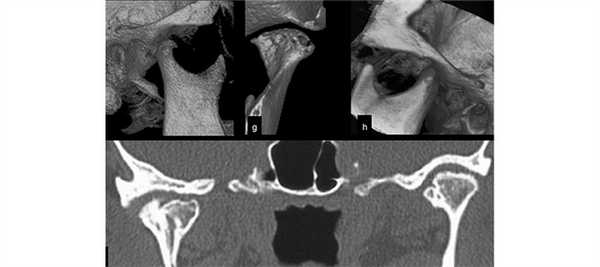

Разновидности обследования

КТ ВНЧС может проводиться с закрытым и открытым ртом, в зависимости от конкретного клинического случая. Во время проведения процедуры могут использоваться различные варианты этого обследования:

- Траснаксиальная методика. Это стандартная процедура (через ось тела). В ходе ее проведения получается порядка 25 снимков, идущих параллельно глазной ямке. Можно визуализировать отдельно левый и правый сустав.

- Саггитальное сканирование. Оно проводится строго параллельно ушной раковине. Ведется оценка состояния ВНЧС в трех фазах, т.е. пациента просят закрыть рот, приоткрыть его наполовину и полностью.

- Объемный 3D-режим. Получается пространственное изображение правого и левого сустава.

Как правило, во время диагностики используется комбинация из вышеуказанных вариантов обследования для получения наиболее точной картины.

Благодаря сканированию в аксиальной проекции, КТ височно-нижнечелюстных суставов позволяет воссоздать форму костных суставных поверхностей, оценить состояние сочленения и прилегающих тканей.

КТ височно-нижнечелюстных суставов в трех взаимно перпендикулярных проекциях дает возможность воссоздать достоверную 3D-модель, где будут отражены малейшие изменения суставных элементов, свидетельствующие о развивающихся патологических процессах.

Особенностью КТ височно-нижнечелюстных суставов является комбинация различных методов сканирования:

прямое сагиттальное сканирование - оценивают состояние ВНЧС при смене положения, для чего пациента просят открыть рот, оставить полуоткрытым и закрыть полностью;

стандартное трансаксиальное сканирование через ось тела - показывает состояние каждого сустава в отдельности;

стандартное 3D-сканирование - с его помощью получают объемное изображение правого и левого ВНЧС.

Проведение КТ височно-нижнечелюстных суставов с использованием трех программ гарантирует полноту информации и дает возможность дифференцировать заболевание и поставить точный диагноз.